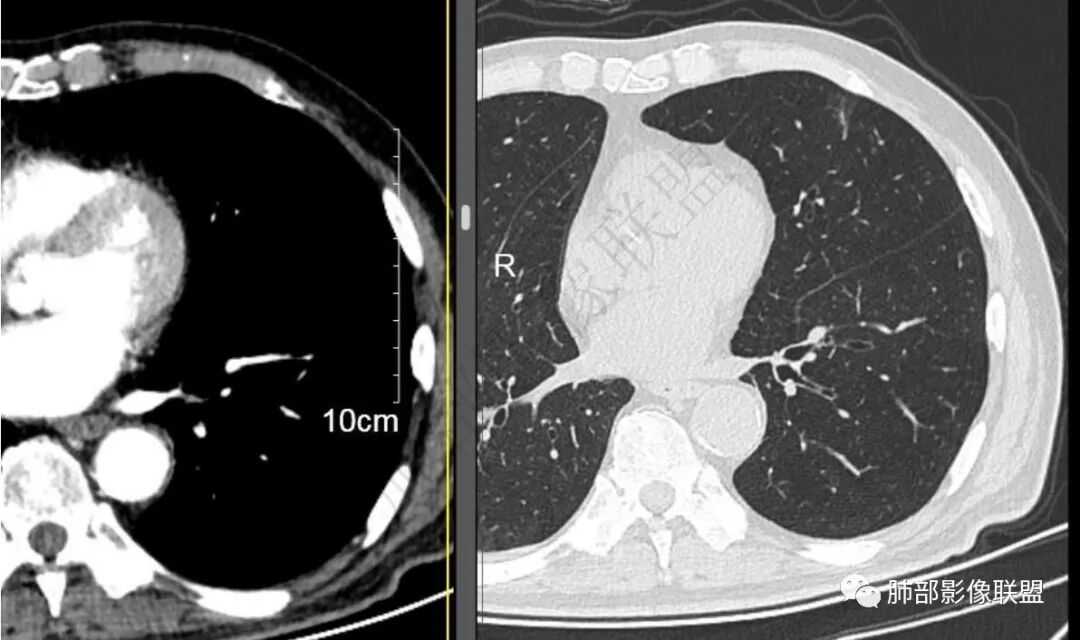

再1个多月后病灶继续增大,较明显不均匀强化,肺门一侧见低密度区。病灶边缘相对不清,可见毛刺。